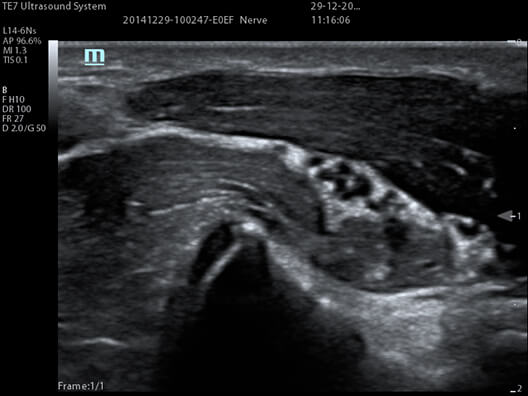

iNeedle

Dla głowic liniowych i convex dostępna jest funkcja zaawansowanej wizualizacji igły iNeedle. Technologia ta znacznie poprawia obraz igły podczas procedury In-Plane (kłucia w płaszczyźnie obrazowania).